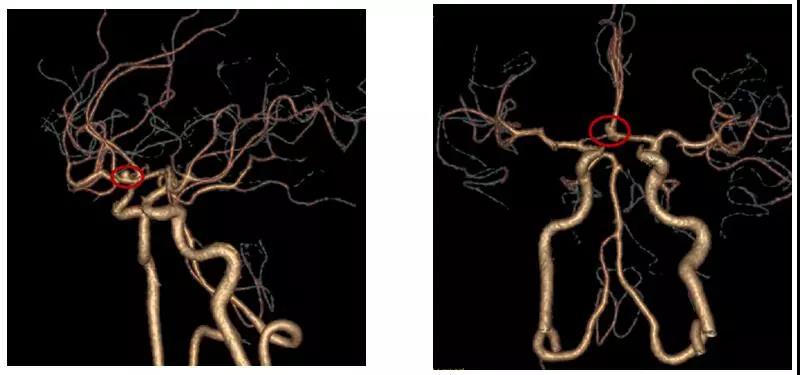

今年52岁的赖先生在外院检查发现颅内动脉瘤1周,为求进一步治疗前来惠州三院,头颅CTA检查提示:前交通动脉瘤。患者既往有糖尿病3年和高血压1年病史,未进行正规治疗和监测。

患者术前头部CTA

患者术后头部CTA